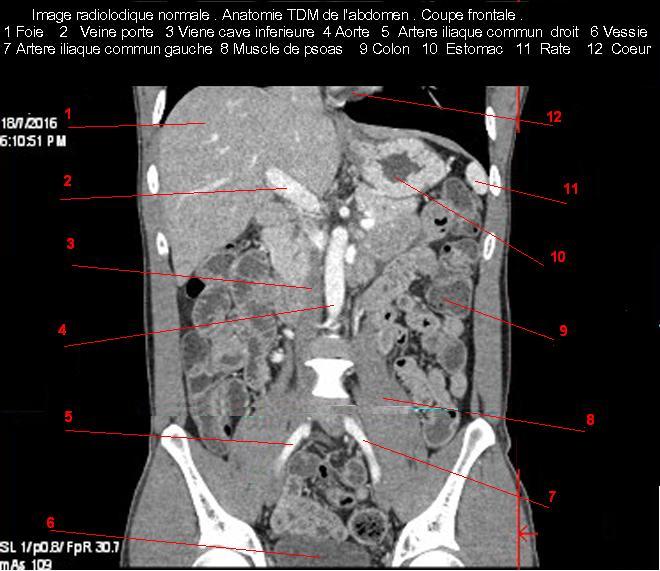

Image TDM de l'abdomen en

coupe coronale ( frontale)avec contrast iode . Veine

porte branche droit et gauche sont en vue |

Aspect normale de la veine

porte commun en coupe TDM coronale . |